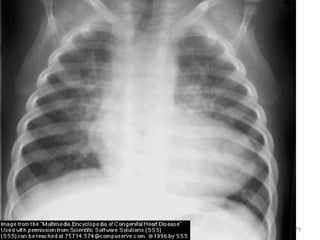

Acyanotic CHD…

Diagnosis

- Clinical

- CXR - Cardiomegaly

- Plethoric lung

- ECG

- Echocardiography